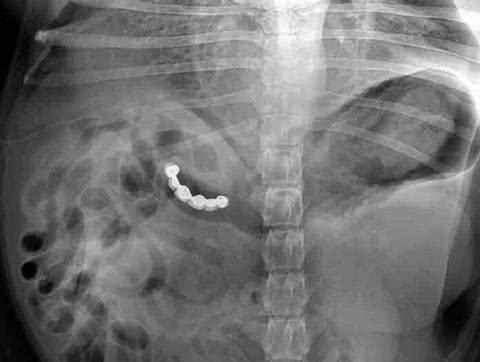

​↓这个太搞笑,吃个饭牙套都给吞了!

看X光下那些意外进入身体的异物!个个奇葩搞笑